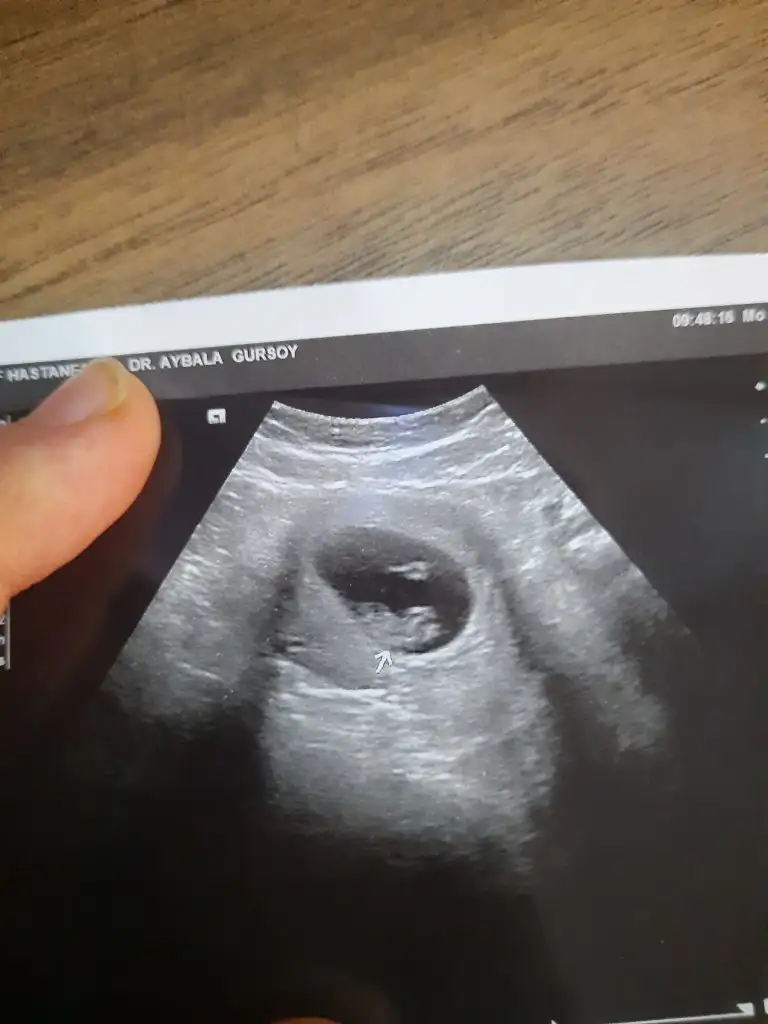

11 haftalık yorum yaparmısınız

• 20220929_121220.webp

20220929_121220.webp

12,2 KB · Görüntüleme: 87